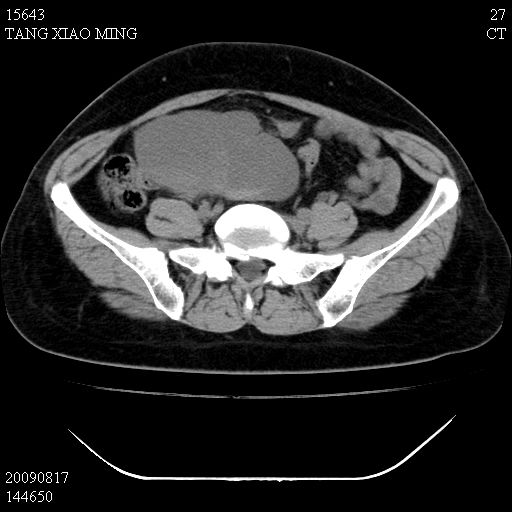

标题: CT21692:盆腔病变

女,33岁,右下腹痛2年余,既往宫外孕病史,如在我院手术,结果下周公布,

可能的诊断。1子宫内膜异位【子宫腺肌症并右卵巢巧克力囊肿】;2 右卵巢囊腺瘤。子宫肌瘤

1)考虑卵巢巧克力囊肿,不排除卵巢囊腺瘤。2)子宫肌瘤可能。

卵巢囊腺瘤,子宫肌瘤,直肠壁厚,不除外占位.